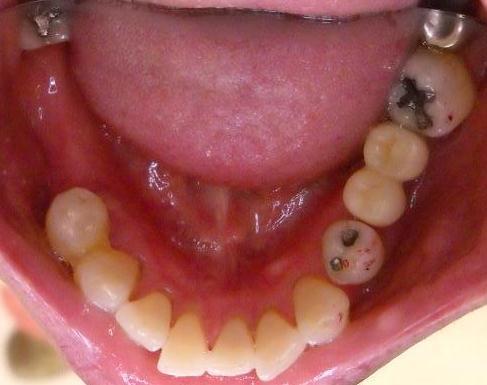

【審美歯科・奥歯症例】

●白い歯(セラミックス)

ハイブリッドクラウン 3本

上記費用目安

初診検査 3500

グラスファイバーコア 20000×2本 15000×1本

仮歯 2000×3本

歯型 5500

ハイブリッドセラミック 39800×3本

調整装着費用 5500

■ポイント■

比較的安価で白い歯が可能、やや耐久性に問題があり

噛み合わせ強い方や歯ぎしりのある方は適応から外れる

奥歯では十分なキレイさ(審美性)

費用が比較的安い

セラミックに比べて 見た目や耐久性は劣る